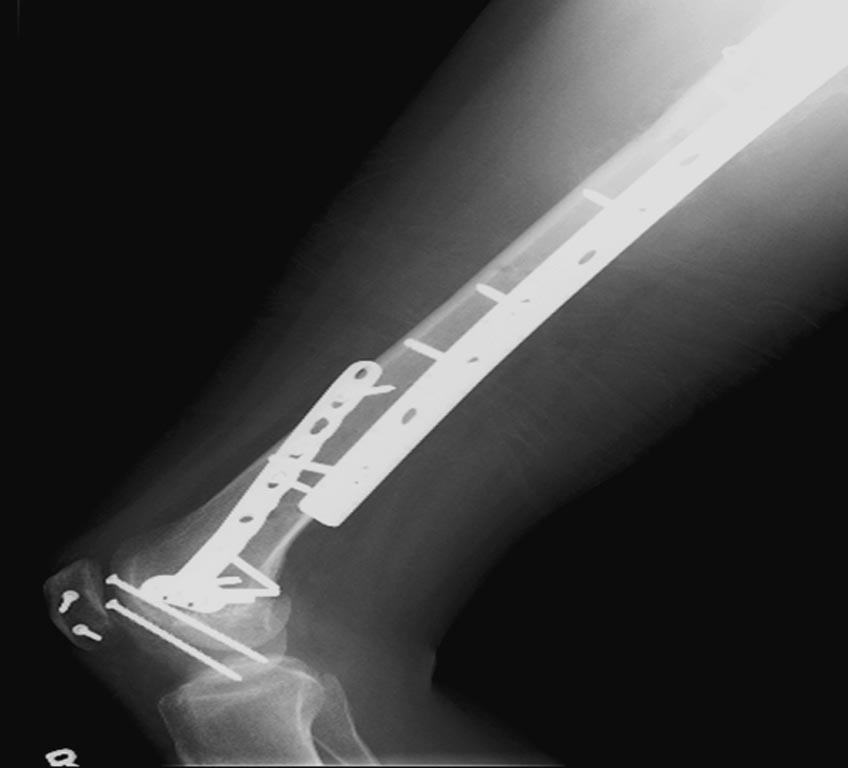

Раны в области коленного сустава и на плече до сих пор чистые, остаются открытыми. Отсутствует признаки инфекции, решили превратить недостаток в преимущество, т.е. фиксировать через открытые раны пластинами.

На 9й день фиксация дистального бедра, где фрагмент Hoffa и вертикальный перелом надколенника, зафиксированы винтами.

На 11й день фиксация плеча также пластиной.

На 25 день с момента травмы операция на Jackson table с боковым обширным доступом. Удаление стержней с местной обработкой. В тазобедренном суставе удаление головки, на дне вертлужной впадины полная отслойка хряща. Вертлужный компонент с одним винтом и короткая ножка - Fitmore press fit stem. На второй день однократно доза радиации для профилактики гетеретопической оссификации. Послеоперационный период без температуры. Выписана. Нагрузку разрешили на левой стороне, а полная в 3 мес. Здесь снимки при амбулаторном наблюдении: послеоперационно, 2 мес, 3 мес и 6 мес. Нагрузка полная, отсутствует хромота, и нет жалоб.